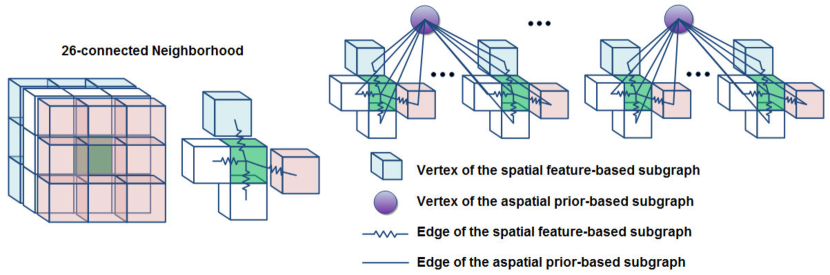

Furthermore, in the original random walker graph for image segmentation, every sample had 8 direct spatial neighbors which was called a second-order or an 8-connected neighborhood in 2D. We extended this to a second-order or a 26-connected neighborhood in 3D which resulted in direct spatial neighbors for each sample (vertex) on the subgraph . Figure 3 shows the 26-connected neighborhood and a portion of the graph involving this kind of neighborhood in its spatial feature-based subgraph . The 26-connected neighborhood allowed the information to propagate across the vertices (samples) of without imposing the complexity of nearest neighbor calculation or any other clustering (grouping) method. In addition, it kept the topology of the subgraph regular and homogeneous to the extent that the derivation of the real valued edge weights of did not result in vanishing of some weights. That is, it could happen that two samples were 26-connected neighbors of each other but their features were so different that their connecting edge weight vanished. In this case, the samples were disconnected.